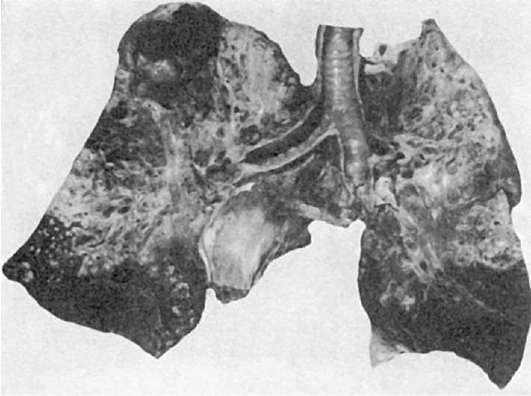

Понимание кавернозного туберкулеза почки

Раздел: Мудрость в деталях